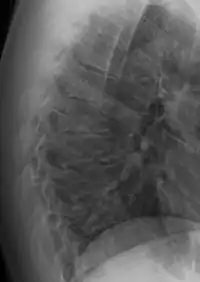

![]() | |

| Scheuermann's disease on lateral Xray of the T spine | |

| Diagnostic method | X-ray, MRI |

Diagnosis is typically by medical imaging. The degree of kyphosis can be measured by Cobb's angle and sagittal balance.